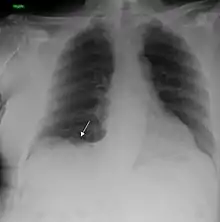

يعدّ التدخين هو السبب الأول لحالات سرطان الرئة حيث يشكل حوالي 85% كسبب رئيسي للإصابة بذلك السرطان وفقط حوالي 10-15٪ من حالات السرطان تحدث عند الأشخاص الذين لم يدخنوا أبدًا.[9][10][11][12] غالبًا ما تنتج هذه الحالات عن مجموعة من العوامل الوراثية مثل التعرض لغاز الرادون، أو الأسبستوس، أو التدخين غير المباشر، أو أشكال أخرى من تلوث الهواء. يمكن رؤية سرطان الرئة على الصور الشعاعية للصدر والتصوير المقطعي المحوسب (CT). يتم تأكيد التشخيص عن طريق الخزعة.[13]

- الأشعة السينية[7]